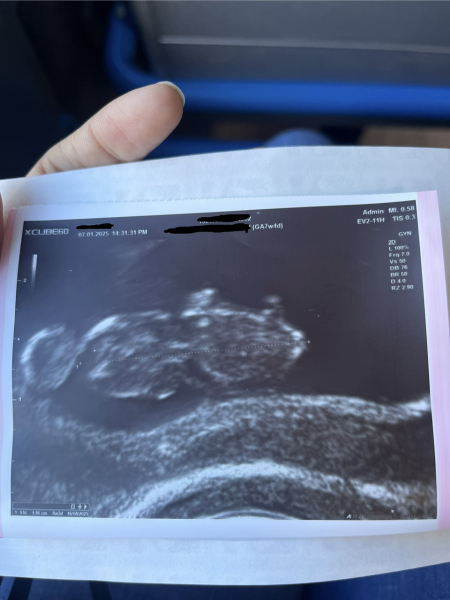

Good morning! I know this is a TTC thread, but I stayed cause I wanted to follow the journey of us who started TTC together and you said you wanted to follow my journey's updates as long as you're here.. so I'll update from yesterday 😊 that I had my first scan :) Everything went good, measuring 8w3d, two days ahead of what I had calculated and 1 week ahead of lmp (but that I knew cause I knew I ovulated early). Really happy that everything is in place and developing as it should ♥️🙏🏼

@pcbrb ahh I’m so glad you’re still here 🥰 so happy for you and how lovely to see your little baby 🥹🥹 when’s your due date? X

@Em3009 it would be 16th of August 2025 😊♥️